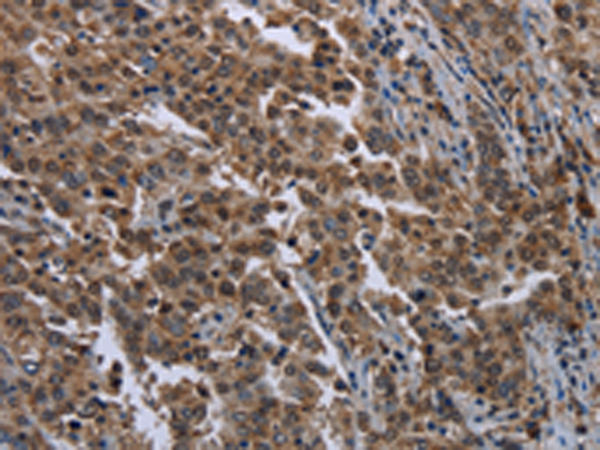

分类: 科研抗体货号: P08400别名: KMT7; SET7; SET9; SET7/9应用: IHC反应种属: Human, Mouse